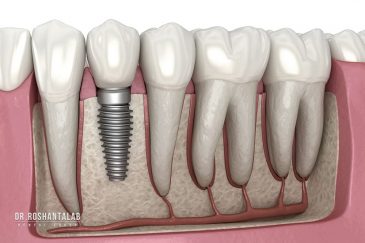

🔸 کاشت ایمپلنت دندان بدون درد

🔸 کاشت دندان یک روزه ( کشیدن و کاشت همزمان )

🔸 ایمپلنت دیجیتال و ساخت روکش دیجیتال

تجربه کاشت دندان دیجیتال و بدون درد در ۳ دقیقه! استفاده از برترین برندها زیر نظر جراح، با هزینه مناسب و خدمات کامل از کاشت دندان تا روکشارتودنسی دندان

انتخاب بهترین متخصص ایمپلنت که به تکنیکهای روز دنیا مسلط باشد، تضمینکننده سلامت فک و زیبایی لبخند شماست. در کلینیک دندانپزشکی دکتر روشنطلب، ما با بهرهگیری از تجهیزات دیجیتال در ۵ شعبه فعال (تهران، اصفهان، رشت و استانبول ترکیه)، خدمات تخصصی کاشت ایمپلنت دندان را برای بیمارانی که کیفیت و دقت برایشان اولویت دارد، ارائه میدهیم. در این متد، پروسه درمان با ظرافت بالا انجام شده؛ راهکاری ایدهآل برای کسانی که به دنبال درمان بدون درد با بالاترین نرخ موفقیت هستند.